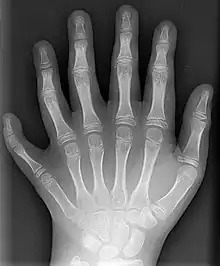

La polydactylie (du grec « poly » : « nombreux » et « dactyle » : « doigts ») se définit comme la présence d’un ou plusieurs doigts supplémentaire(s) au niveau de la main ou d’un ou plusieurs orteils au niveau du pied. Les gènes induisant le développement de la polydactylie sont toujours présents chez les formes actuelles, ce qui suggère que dans l'histoire évolutive du vivant, la polydactylie apparaît comme la condition plésiomorphe pour les tétrapodes, c'est-à-dire la condition primitive initiale du membre marcheur, la pentadactylie n'étant pas la disposition « canonique » de la structure de ce membre marcheur[1].

La polydactylie de la main est la plus fréquente des malformations de la main, l'hexadactylie (6 doigts ou orteils) la plus fréquente des polydactylies (1,7 cas pour mille naissances)[4]. On distingue classiquement la polydactylie « préaxiale » de la polydactylie « postaxiale », bien que certains contestent cette classification.